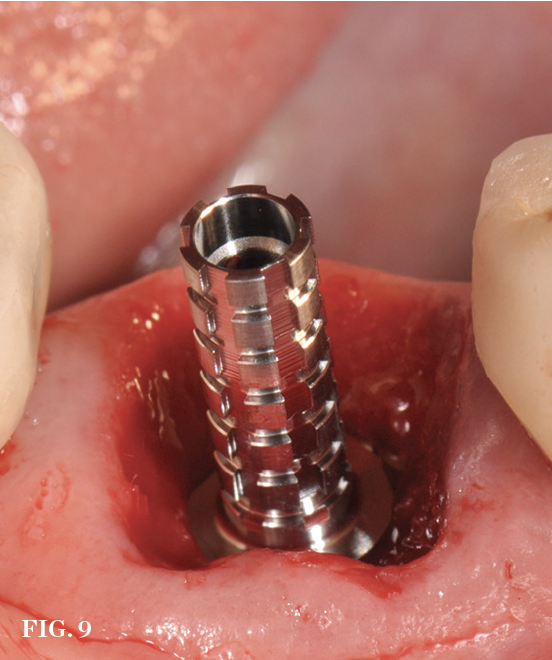

(9.) Chairside custom healing abutment fabrication in progress using a temporary abutment.

Figure 9